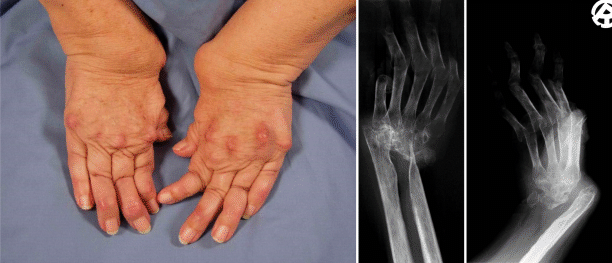

Operative Therapie Bei Rheumatoider Arthritis Der Hand